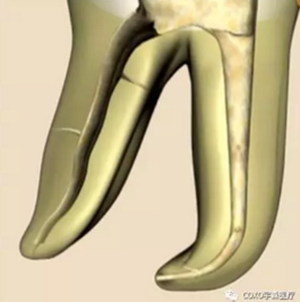

( 2 )髓腔其他改變:如髓室頂、繼發(fā)性牙本質(zhì)、修復(fù)性或增齡性牙本質(zhì)。見左圖。

右圖中有繼發(fā)性牙本質(zhì),切削后獲得直線通路。